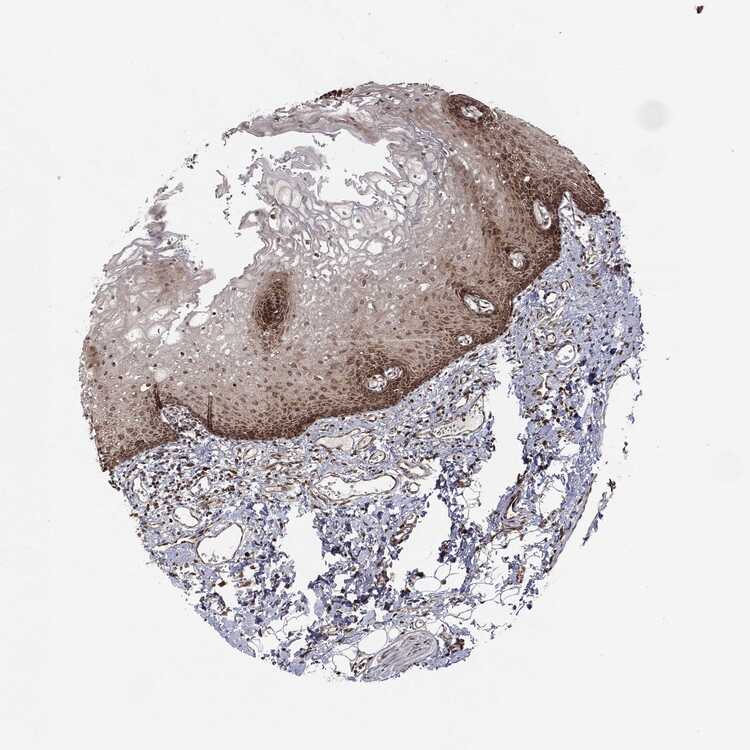

TISSUE PRIMARY DATA ORAL MUCOSA Show tissue menu

ORAL MUCOSA - Antibody stainingi

Antibody staining in the annotated cell types in the current human tissue is reported as not detected, low, medium, or high, based on conventional immunohistochemistry profiling in selected tissues. This score is based on the combination of the staining intensity and fraction of stained cells.

Each image is clickable and will lead to virtual microscopy that enables deeper exploration of all samples and also displays staining intensity scores, fraction scores and subcellular localization as well as patient and tissue information for each sample.

Antibody HPA039176Antibody CAB080075

Squamous epithelial cells LowMedium